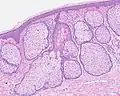

Sebaceous hyperplasia

Sebaceous hyperplasia is a disorder of the sebaceous glands in which they become enlarged, producing flesh-colored or yellowish, shiny, often umbilicated bumps on the face.[1] Newly formed nodules often swell with sweating (which is pathognomonic for the condition), but this diminishes over time.

Sebaceous hyperplasia generally affects newborns as well as middle-aged to elderly adults. The symptoms of this condition are 1–5 mm papules on the skin, mainly on the forehead, nose and cheeks, and seborrheic facial skin. The papules may be cauliflower-shaped. In infants, acne is sometimes associated with sebaceous hyperplasia.